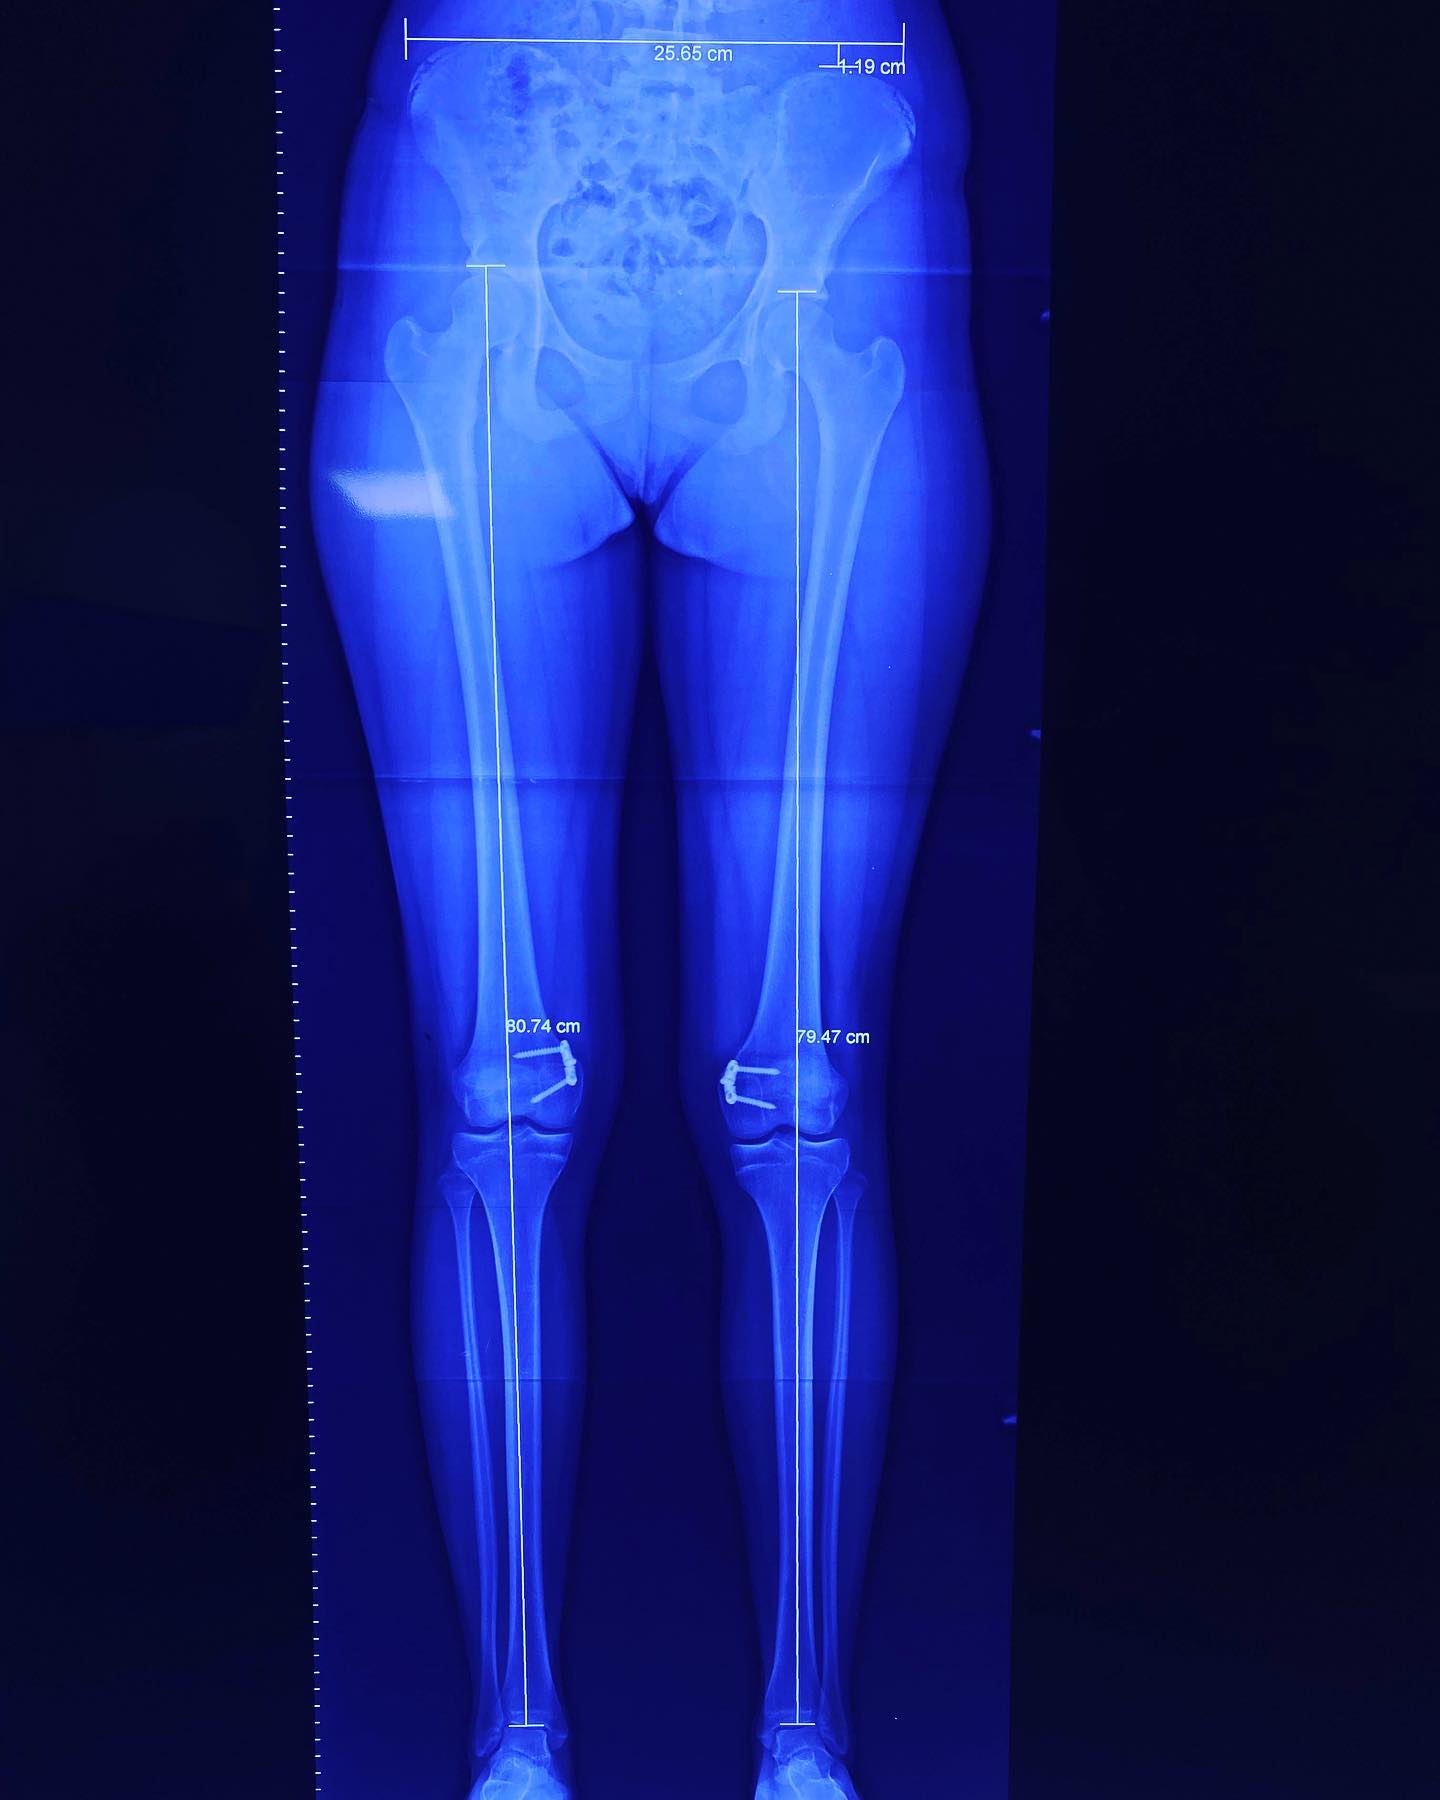

deformidad rodillas en valgo

Ella es mi pacientita Danna, de 13 años. Vino a consulta por una deformidad muy común: “rodillas en valgo”. Por suerte, llegó a tiempo y logramos corregirla al 💯. ¡Felicidades, Danna! Ahora sí, ¡a darle al gym! 💪 💪🏻